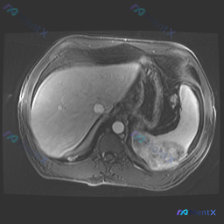

看到一个很有警示意义的影像病例,整理一下思路和大家分享: 最初的影像描述 这是一张腹部MRI轴位T2加权图像,可见一个边界清晰、形态规则的类圆形极高信号病灶,信号强度接近脑脊液(典型的“灯泡征”样表现),内部信号均匀,无明显分隔、结节或壁增厚,也未见对周围组织造成明显压迫或占位效应。 第一个容易踩的...

整理了一份脾脏占位的读片+分析思路,感觉这个病例的「混杂信号」挺有代表性,容易被带偏,分享出来一起理一理。 --- 一、先看影像核心表现 这份是上腹部MRI轴位T2加权像: - 肝脏、胃壁、腹膜后大血管这些都还好,没见明显异常; - 脾脏形态正常,但里面有一个类圆形占位,边界尚清; - 关键信号:T...

整理了一份很有警示意义的影像读片思路,分享给大家。 --- 核心影像资料(腹部MRI轴位T2加权) 先看图像里的明确表现: 1. 胆囊:右侧腹部高信号(亮白),符合胆汁充盈的T2表现,未见明显充盈缺损 2. 右肾:中等信号,肾盂肾盏少量液体信号 3. 左肾(影像右侧):肾实质内见圆形高信号区,边缘锐...